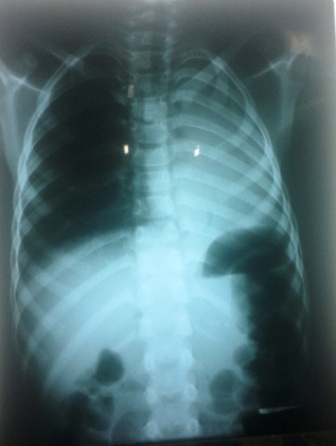

Tại đây, cháu Hào được các bác sĩ Khoa Hồi sức cấp cứu - điều trị tích cực khám và chẩn đoán có dị vật đường thở, nghi do chiếc nắp đầu bút bi bằng nhựa rơi vào phế quản góc bên trái. Qua chụp X-Quang thấy mờ toàn bộ phổi trái. Ngay sau đó, các bác sĩ đã tiến hành nội soi phế quản cháu Hào, xác định vị trí dị vật và dùng phương pháp nội soi gắp thành công chiếc nắp đầu bút bi trong phế quản cháu Hào.